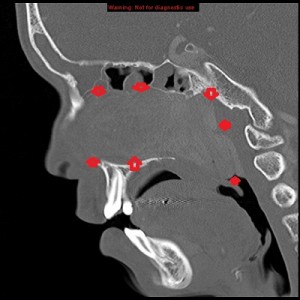

Third panel, left to right: The first 2 images are coronal sections of the face showing the mass-effect of the left nasal mass on other surrounding structure.The third image in this panel is a sagittal paramedian section showing obstruction of the nasopharynx by a soft-tissue mass.